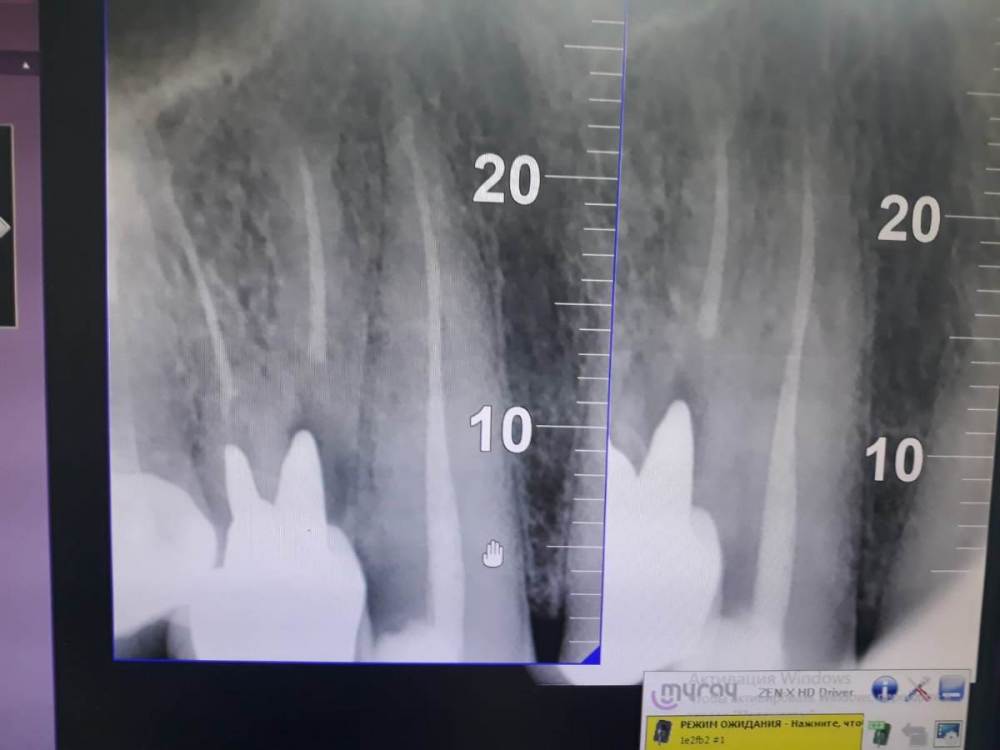

Людмила79 Опубликовано 1 июля, 2022 Поделиться Опубликовано 1 июля, 2022 Здравствуйте. Обратилась к стоматологу с воспалением верхней десны, образовался гнойник около коронки на штифте. Данной коронке примерно 15 лет. Гнойник вскрыли, но он появляется вновь и вновь. Врачи говорят, что в данном случае возможно только удаление зуба, т.к. инфекция располагается глубоко, кариес находится под вкладкой (прикорневой кариес). Мне конечно жаль "расставаться" с зубом. Хочется быть на 100 % уверенной в том, что действительно удаление- единственный возможный вариант. Может быть всё же можно снять коронку и вкладку и вы лечить канал? Спасибо. Ссылка на комментарий

Гарриевич Опубликовано 1 июля, 2022 Поделиться Опубликовано 1 июля, 2022 Большие подозрения что да, сохранение маловероятно Ссылка на комментарий